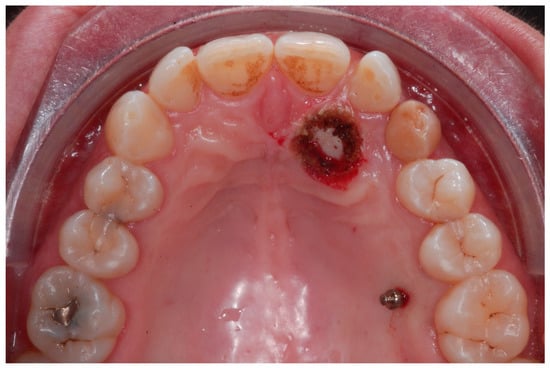

The therapeutic choice was to start with mini-invasive laser gingivectomy (Figure 11) followed immediately by traction by means of TAD direct anchorage. In order to reduce bone resistance, a piezocision cut (Figure 12) along the eruption path of the canine was performed. The biomechanics system for force eruption consisted of a piece of mesh (Leone, Italy), precisely cut to fit the palatal side of the canine, connected to a 150 g coil spring by means of a metallic ligature (Figure 12). The TAD (HDC Spider Pin, 1.3 mm wide and 10 mm long) was inserted on the palatial side mesially to the first molar and then connected to the coil spring. Thus, the extrusion vector was diagonal and horizontal in order to move the crown tip far away from the lateral incisor, and, at the same time, it was vertical in order to produce extrusion (Figure 13).

Figure 11.

Mini-invasive laser gingivectomy.

Figure 12.

A piezocision cut carried out along the eruption path of the canine in order to reduce bone resistance.